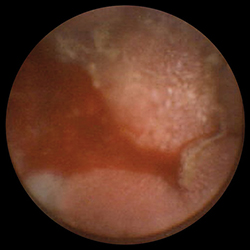

Именно поэтому внедрение в 2001 г. в широкую гастроэнтерологическую практику капсульной эндоскопии было воспринято многими как революционный шаг в инструментальном исследовании тонкого кишечника. Благодаря этой методике стало возможным практически безболезненно и комфортабельно как для врача, так и для пациента, получить достаточно достоверную информацию о доселе бывшей «terra inсognita» для гастроэнтерологов и эндоскопистов части желудочно-кишечного тракта — тощей кишке.

Принцип работы этой небольшой (размерами 26×11 мм и весом всего в 3,7 г) и поэтому вполне «удобоваримой» капсулы заключается в передаче высококачественных цифровых снимков тонкого кишечника на приемник, находящийся в поясе на теле пациента в течение всего исследования. Сама капсула состоит только из камеры, источника света, передающего устройства и занимающей больше всего места батареи, емкость которой позволяет, однако, сделать более 55 000 (!) снимков с частотой 2 снимка в секунду на протяжении 6 ч, чего оказывается, как правило, вполне достаточно для составления целостной картины обо всем тонком кишечнике. Естественно, что такое количество снимков сначала анализируется соответствующей компьютерной программой и уже ее результаты в виде «короткометражного» фильма оценивает гастроэнтеролог.

И доверие это вызвано в первую очередь обнадеживающими результатами в диагностике желудочно-кишечных кровотечений (ЖКК) неустановленного генеза. Составляя менее 5% всех ЖКК, именно они являются настоящим тактическим вызовом как для гастроэнтеролога, так и для хирурга. Операции «на высоте» кровотечения, призванные локализовать неизвестный его источник, оказываются зачастую роковыми для декомпенсированного тяжелой кровопотерей организма, с другой стороны, выжидательная тактика оправдывает себя только в случае спонтанного гемостаза. Кроме того, нелокализованный источник кровотечения, как правило, дает о себе знать уже в ближайшем будущем. Именно капсульная эндоскопия является наиболее эффективной (чувствительность до 89%, специфичность до 95%, Pennazio M. et al., 2004) по сравнению со всеми имеющимися сегодня диагностическими методиками, когда речь идет о диагностике «средних», как их сегодня часто называют в западной литературе, ЖКК (табл. 1, 2).

Немного по-другому выглядит ситуация с показаниями к капсульной эндоскопии при других патологиях тонкого кишечника — несомненна ее польза в диагностике различных полипозов (FAP-Syndrom (семейный наследственный полипоз), Peutz — Jaghers Syndrom) в первую очередь для планирования дальнейшей лечебной тактики и решения вопроса о необходимости хирургического вмешательства. Аналогичные показания касаются и пациентов с болезнью Крона, хотя в этом случае необходимо считаться с опасностью наличия стенозов и свищей — одного из наиболее частых ее осложнений, — являющихся прямым противопоказанием к капсульной эндоскопии. Для таких случаев была специально разработана Patency-Капсула, оболочка которой частично растворяется под влиянием кишечного содержимого — в результате к концу исследования она превращается в мешочек с соответствующим содержимым и может беспрепятственно преодолеть все стенозы и спайки. Насколько это, несомненно, оригинальное, но и не менее дорогостоящее решение найдет широкое признание в эндоскопической практике — вопрос времени. Достаточно шаткими являются и показания к капсульной эндоскопии в диагностике опухолей, и главным лимитирующим фактором здесь выступает уже упомянутая выше невозможность биопсии.